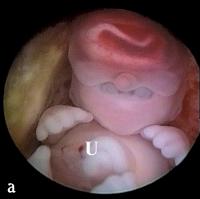

Triploider Embryo

Abbildung 6a-b: Vorderansicht (a) und Seitenansicht (b) eines triploiden (69,XXY) Embryos mit einer SSL von 21 mm. Eine einzige Orbita enthält 2 Augen (Synophthalmie). Es ist eine Rüsselnase vorhanden (Pfeil), die sich oberhalb des Medianauges befindet. Darmschlingen finden sich im proximalen Abschnitt der Nabelschnur (U) (physiologischer Nabelbruch).